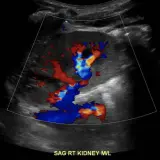

Ultrasound

75 cases Covering OB/GYN, GI/GU, and more